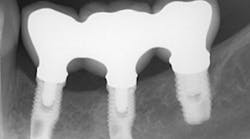

The same arguments have been advanced for not splinting adjacent implants in segmental reconstructions (figure 1). Plaque-related peri-implantitis is the most common biological complication in implant dentistry. A passive fit of prostheses on their supporting implants is considered essential for minimizing mechanical and biological overloading. On the other hand, it is also claimed that splinting can prevent overloading (figure 2). Screw loosening and fracture of veneering material are the most common mechanical complications of loading, although there is little evidence that it results in loss of integration.

Figure 2: Splinted adjacent implants